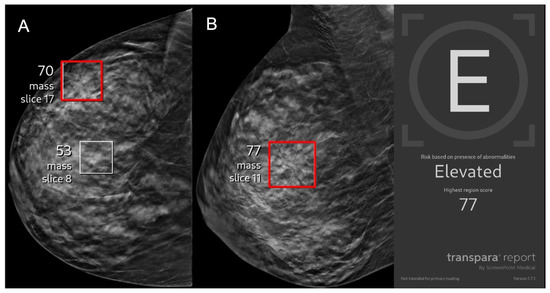

- AI and radiomics in breast imaging;

- Contrast-enhanced and tomographic mammography;